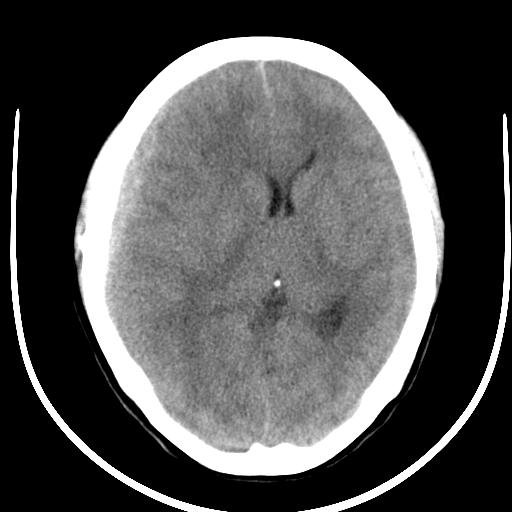

标题: CT16474:急会诊!女36岁。突发头痛头晕呕吐半小时。 [打印本页]

标题: CT16474:急会诊!女36岁。突发头痛头晕呕吐半小时。

请问出血密度为何不高?

2.右顶叶血肿。考虑:血管畸形伴出血。(此种脑出血密度一般比外伤性、高血压性脑出血密度低)

1)右侧额颞顶部硬膜下血肿。2)右侧顶枕叶脑内血肿。3)蛛网膜下腔出血。4)大脑镰下疝。

急性出血 病人可能贫血

图像伪影较大 考虑血肿密度较低的原因:1患者贫血?2、机器伪影所致?

2.右顶叶血肿。考虑:血管畸形伴出血。(此种脑出血密度一般比外伤性、高血压性脑出血密度低) 3.蛛网膜下腔出血不排除

出血的密度改变与出血的时间、部位、出血量及出血后血内成分的变化有关

急性发病,还不到高密度的时候----急性硬膜下血肿 脑内血肿